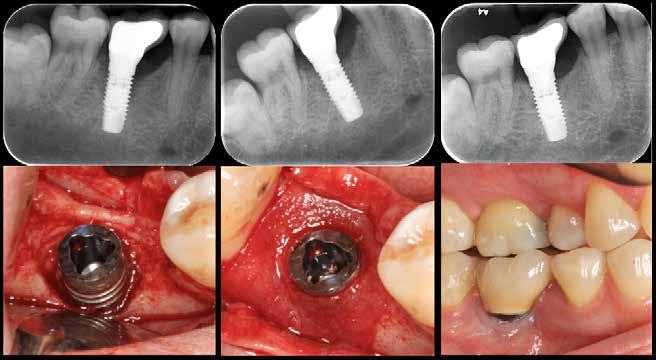

Periimplantær defekt før og efter behandling

Fig. 3. Resektiv kirurgi bedrer den inflammatoriske tilstand, men kompromitterer det æstetiske resultat. Venstre billede: ubehandlet periimplantitis med dybe periimplantære pocher, blødning ved sondering og periimplantært knogletab. Midterste billede: blotlæggelse af knogledefekt, der ikke er velegnet til genopbyggende behandling. Højre billede: efter behandling ses sunde periimplantære forhold med små pochedybder og uden kliniske tegn på inflammation; resultatet er på bekostning af det æstetiske udseende. Fig. 3. Resective surgery improves the inflammatory conditions, but hampers the aesthetic outcome. Left picture. untreated peri-implantitis identified by deep peri-implant pockets, bleeding on probing and peri-implant bone loss. Middle picture: exposure of bone defect, not suitable for reconstructive therapy. Right picture: following treatment, peri-implant health with shallow pockets and no clinical signs of inflammation at the expense of the esthetic outcome.

I forbindelse med den kirurgiske behandlingsfase er man nødt til at beslutte, om indgrebet skal være resektivt, genopbyggende eller en kombination af disse. En vigtig parameter i denne beslutningsproces er morfologien på den periimplantære defekt, da det er morfologien, der afgør mulighederne for knogleregeneration i området. Det er umiddelbart forståeligt, at horisontale knogledefekter har begrænsede muligheder for regeneration (Fig. 3), mens intraossøse defekter har et potentiale for regeneration (Fig. 4). I en systematisk oversigt over dyreforsøg konkluderede man, at udfaldet af knogleregeneration efter kirurgisk behandling af periimplantitis er afhængigt af